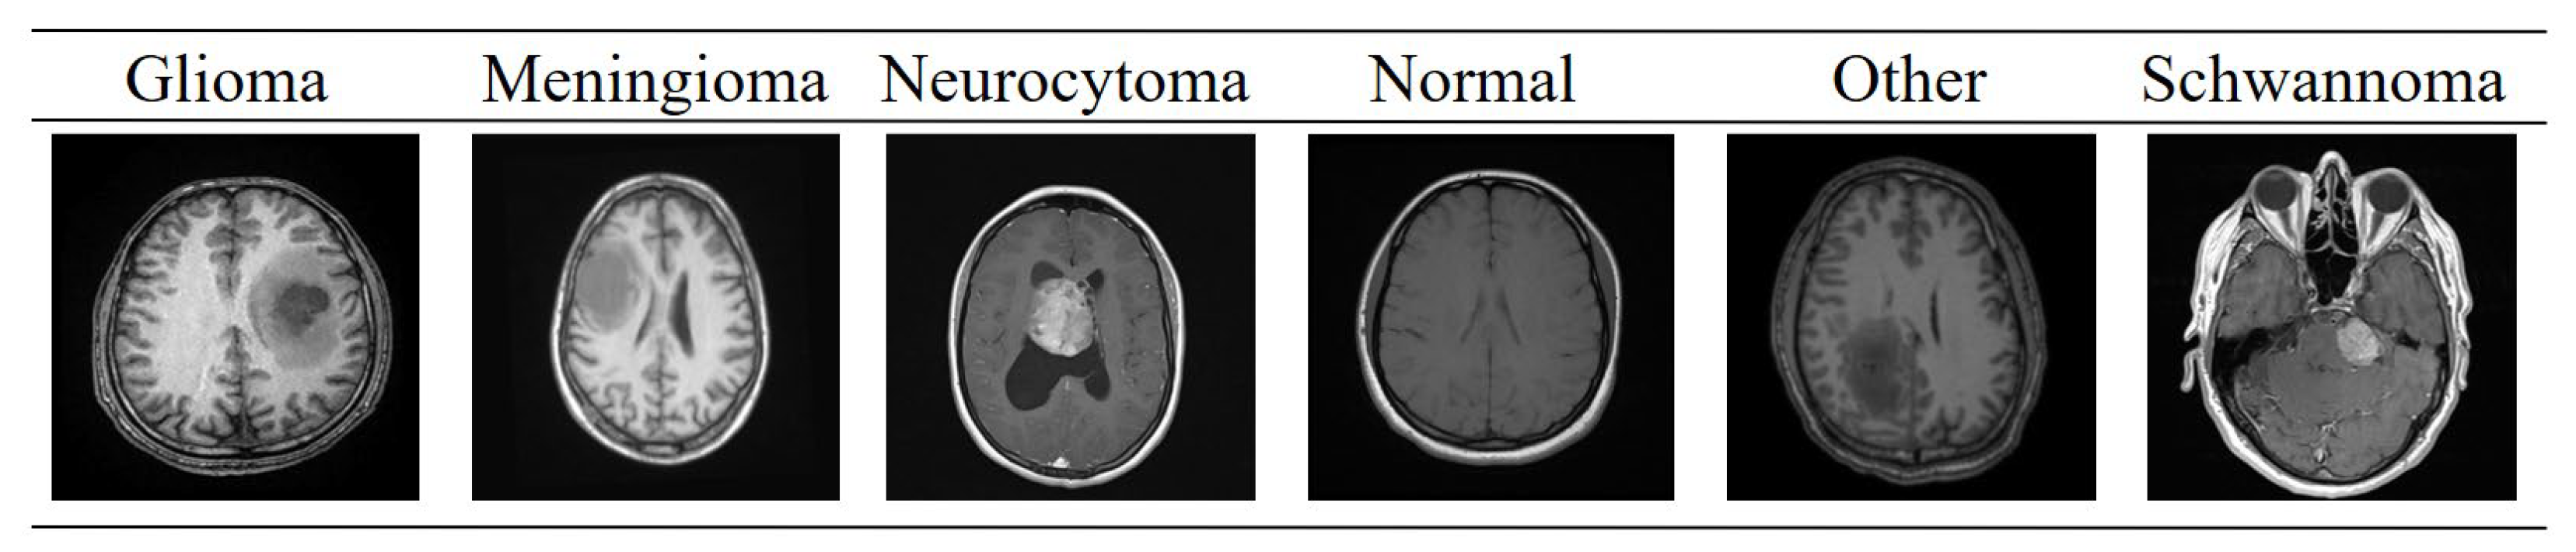

The brain tumor MRI images used in this study were obtained from the BTMRII dataset, shared on the public platform Kaggle [43]. This dataset is an open collection widely referenced in research and comparative experiments. The original BTMRII dataset contains a total of 4448 real MRI images. The images were acquired in the axial plane and include T1, T1-enhanced (T1C+), and T2 modalities with different sequence weights. The original resolution and bit depth of the images may vary within the dataset. Therefore, firstly, all images in the study were rescaled to a uniform network input size of 256 × 256. BTMRII is primarily divided into six classes: Glioma, Meningioma, Neurocytoma, Normal, Other, and Schwannoma. The ‘Normal’ class is divided into two classes: T1 and T2, while the other classes are further divided into three classes: T1, T1C+, and T2, dividing the dataset into a total of 17 different classes. Cataloging is organized with a folder for each class. The set covers a variety of primary brain tumor histologies and some neurological lesion subtypes (example classes: astrocytoma, ependymoma, ganglioglioma, glioblastoma, oligodendroglioma, medulloblastoma, meningioma, pituitary/pituitary adenoma, schwannoma, germinoma, etc.). In this study, the T1, T1C+, and T2 modalities of the six main classes of BTMRII were combined. Thus, 1317 brain MRI images belonging to the Glioma class, 1299 to the Meningioma class, 542 to the Neurocytoma class, 563 to the Normal class, 257 to the Other class, and 470 to the Schwannoma class were used, all in 8-bit and jpeg format. The ground truth annotations were directly obtained from the BTMRII dataset, in which expert radiologists manually delineated the tumor regions on MRI scans. The annotation protocol followed a multi-class segmentation scheme, where each image was labeled with one of the 5 basic predefined tumor categories. For each class, the entire tumor region was annotated as a single mask, rather than subdividing into intra-tumoral components such as necrosis, edema, or enhancing tumor core. Thus, each mask corresponds to a binary segmentation map distinguishing tumor versus non-tumor regions for the respective tumor class. Example images from each of the six classes of the BTMRII dataset are shown in Figure 1.

Figure 1. Sample images from each of the six classes in the BTMRII dataset.